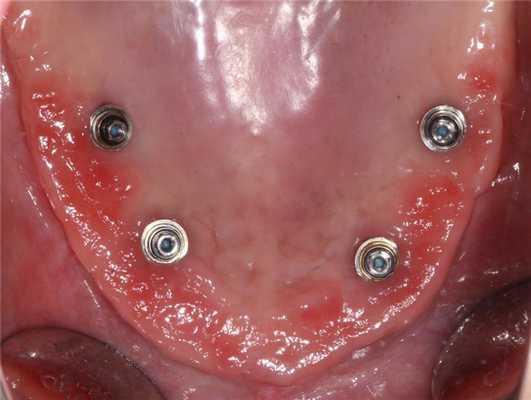

- Выполнение операции по концепции all-on-4 с использованием имплантатов Nobel Parallel CC по классическому протоколу Palo Malo (фото 4)

Через 6 месяцев после операции первичные адаптационные протезы были заменены на новые адаптационные протезы с армированием (фото 18, 19, 20, 21, 22). Фотографии выполнены через 8 месцев после функционирования второго адаптационного протеза. На снимках видно достаточное количество прикрепленной слизистой, которое удалось создать благодаря правильному позициониравнию имплантатов и естественному заживлению после удаления (фото 23, 24).